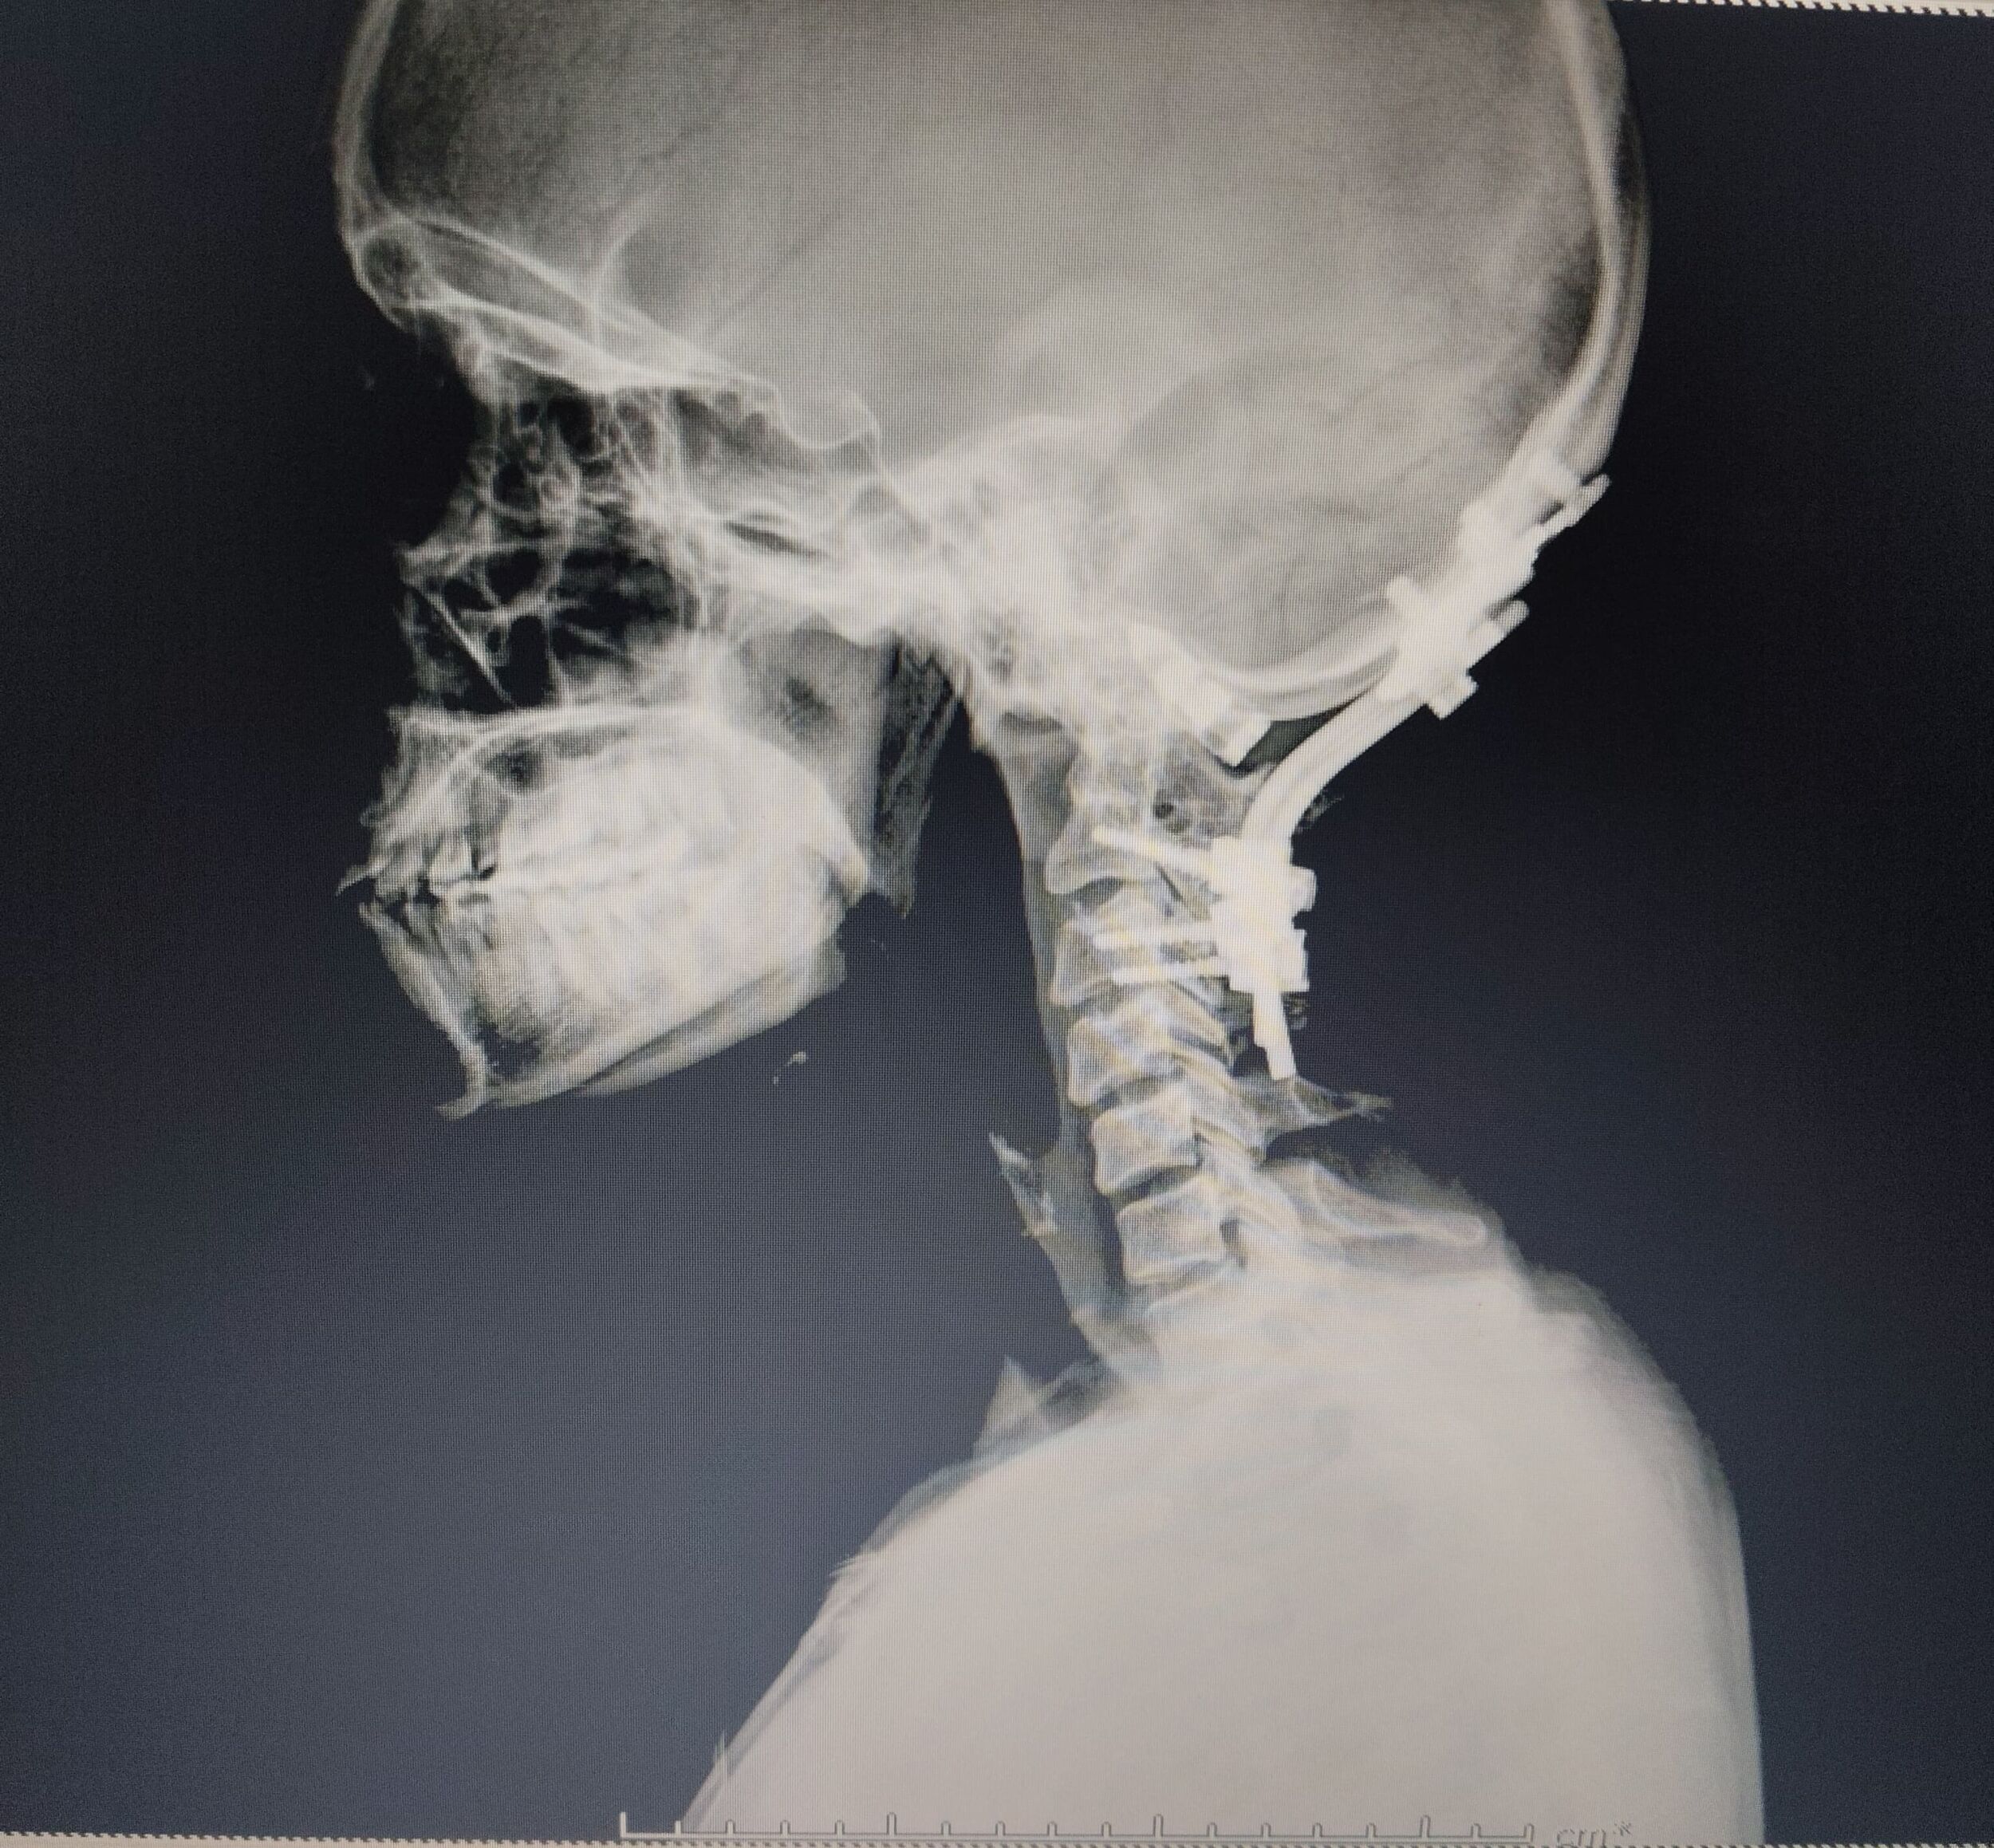

The damaged or slipped disc is removed.

A cage (spacer) filled with bone graft is placed between the vertebrae.

Screws and rods are fixed to support the spine.